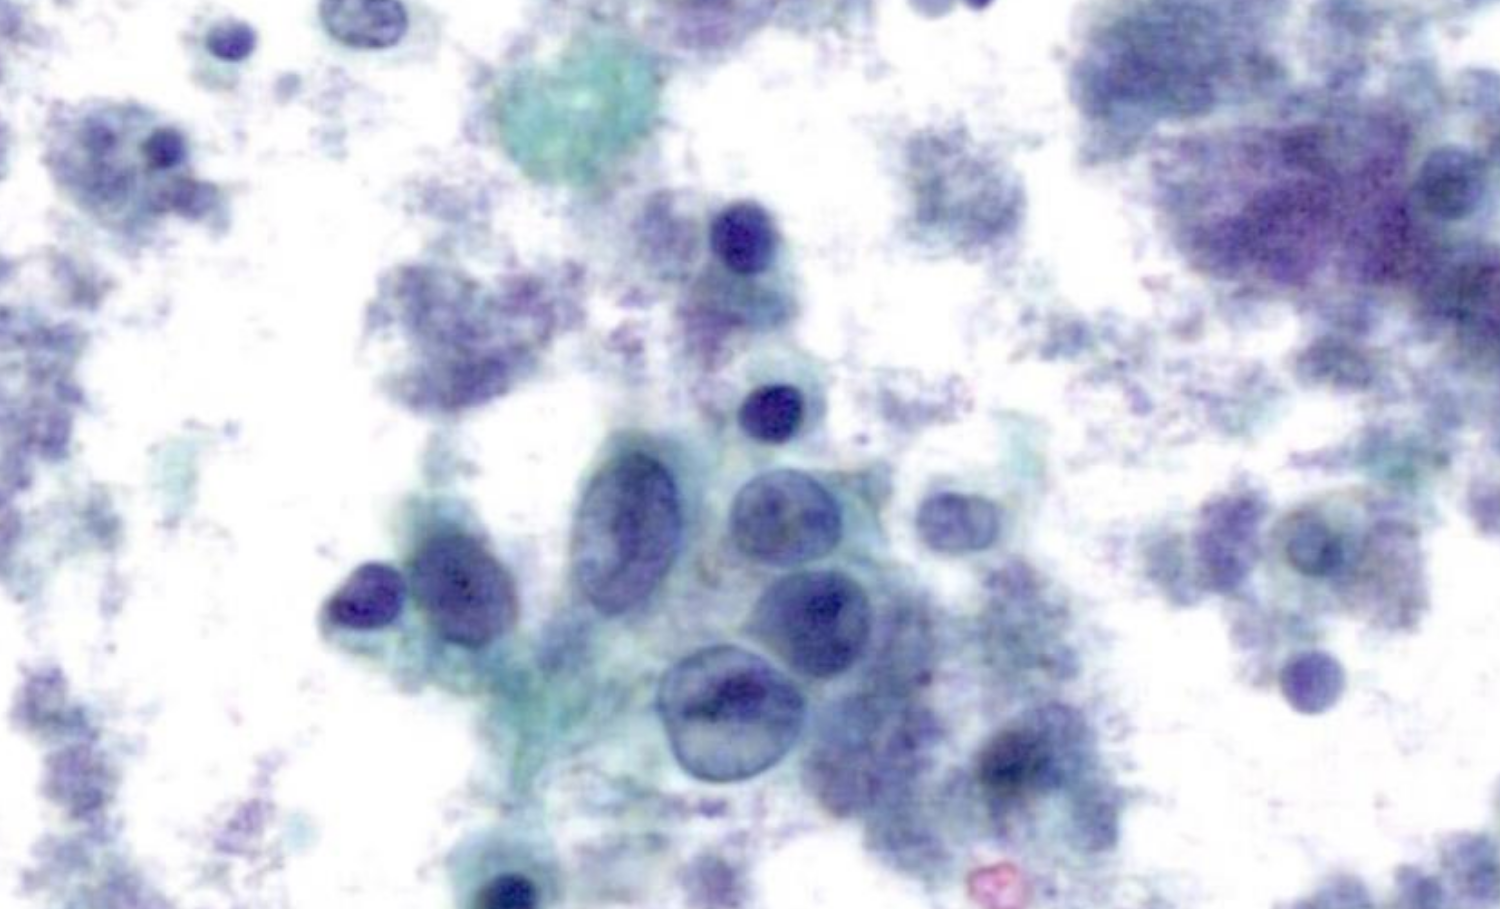

Bladder enteric-type adenocarcinoma is a rare primary malignancy of the urinary bladder, that is predominantly observed in males and accounts for up to 2% of all bladder cancers1. It is characterized by histological and molecular features that closely mimic those of colorectal adenocarcinoma. These include its enteric-type glandular architecture and the frequent expression of intestinal markers such as CDX2 and CK20, as well as the variable CK7 expression2.